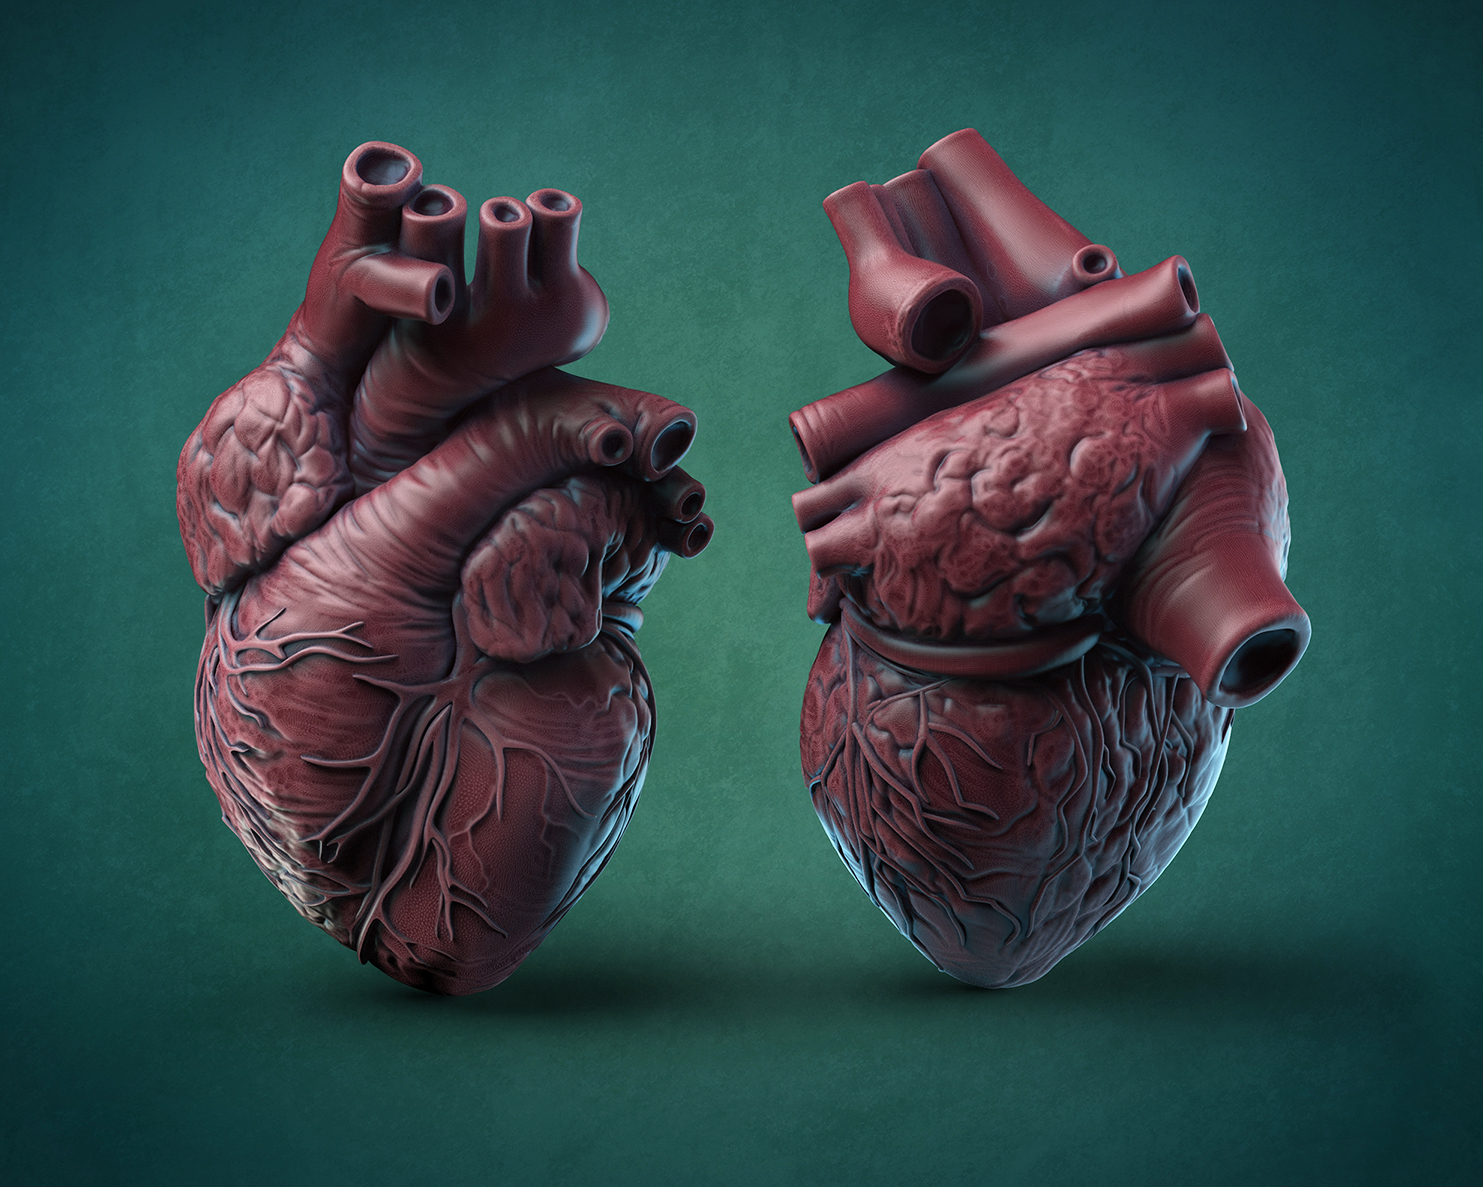

Фотографии и 3D-модели анатомии сердца человека